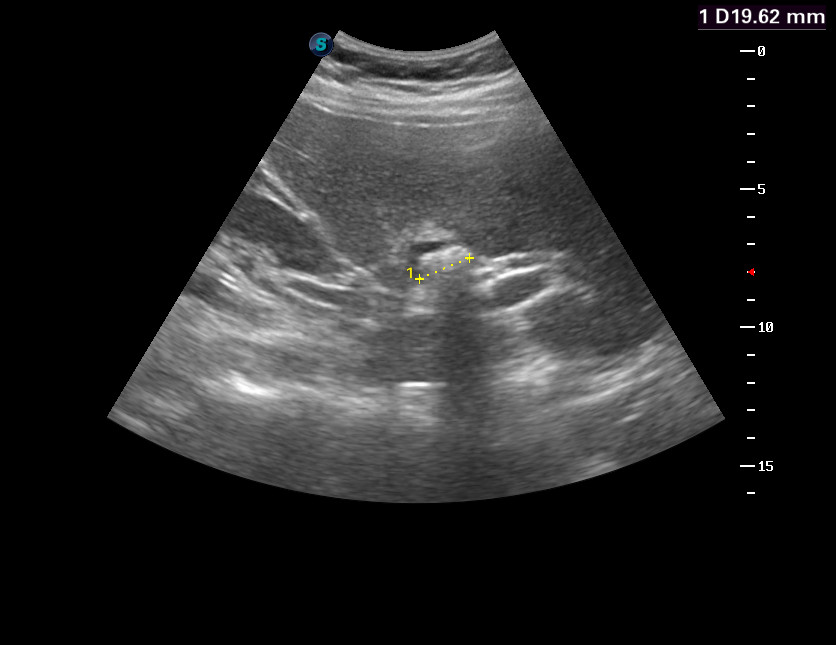

Конкремент культи, микроцистис: УЗИ

Женщина средних лет. Открытая операция холецистэктомии 15 лет назад, в ургентной ситуации.

Конкремент в культе?

Mattiola писал(а):Конкремент в культе?

Да.